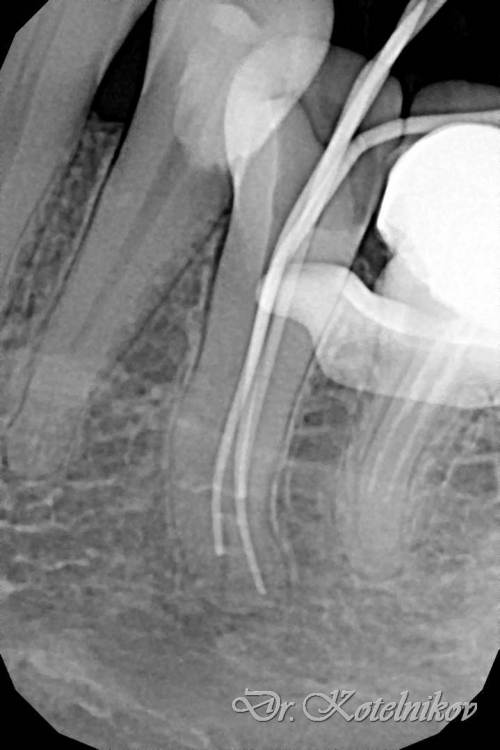

Ico Опубликовано 10 апреля, 2022 Автор Поделиться Опубликовано 10 апреля, 2022 (изменено) 3 отдельных канала в нижнем премоляре,паковка похожая как у Томаса Ланга.Каллибровка,паковка апексов была по S2 протейперу + 25 к. Изменено 10 апреля, 2022 пользователем Ico 1 1 2 Ссылка на комментарий